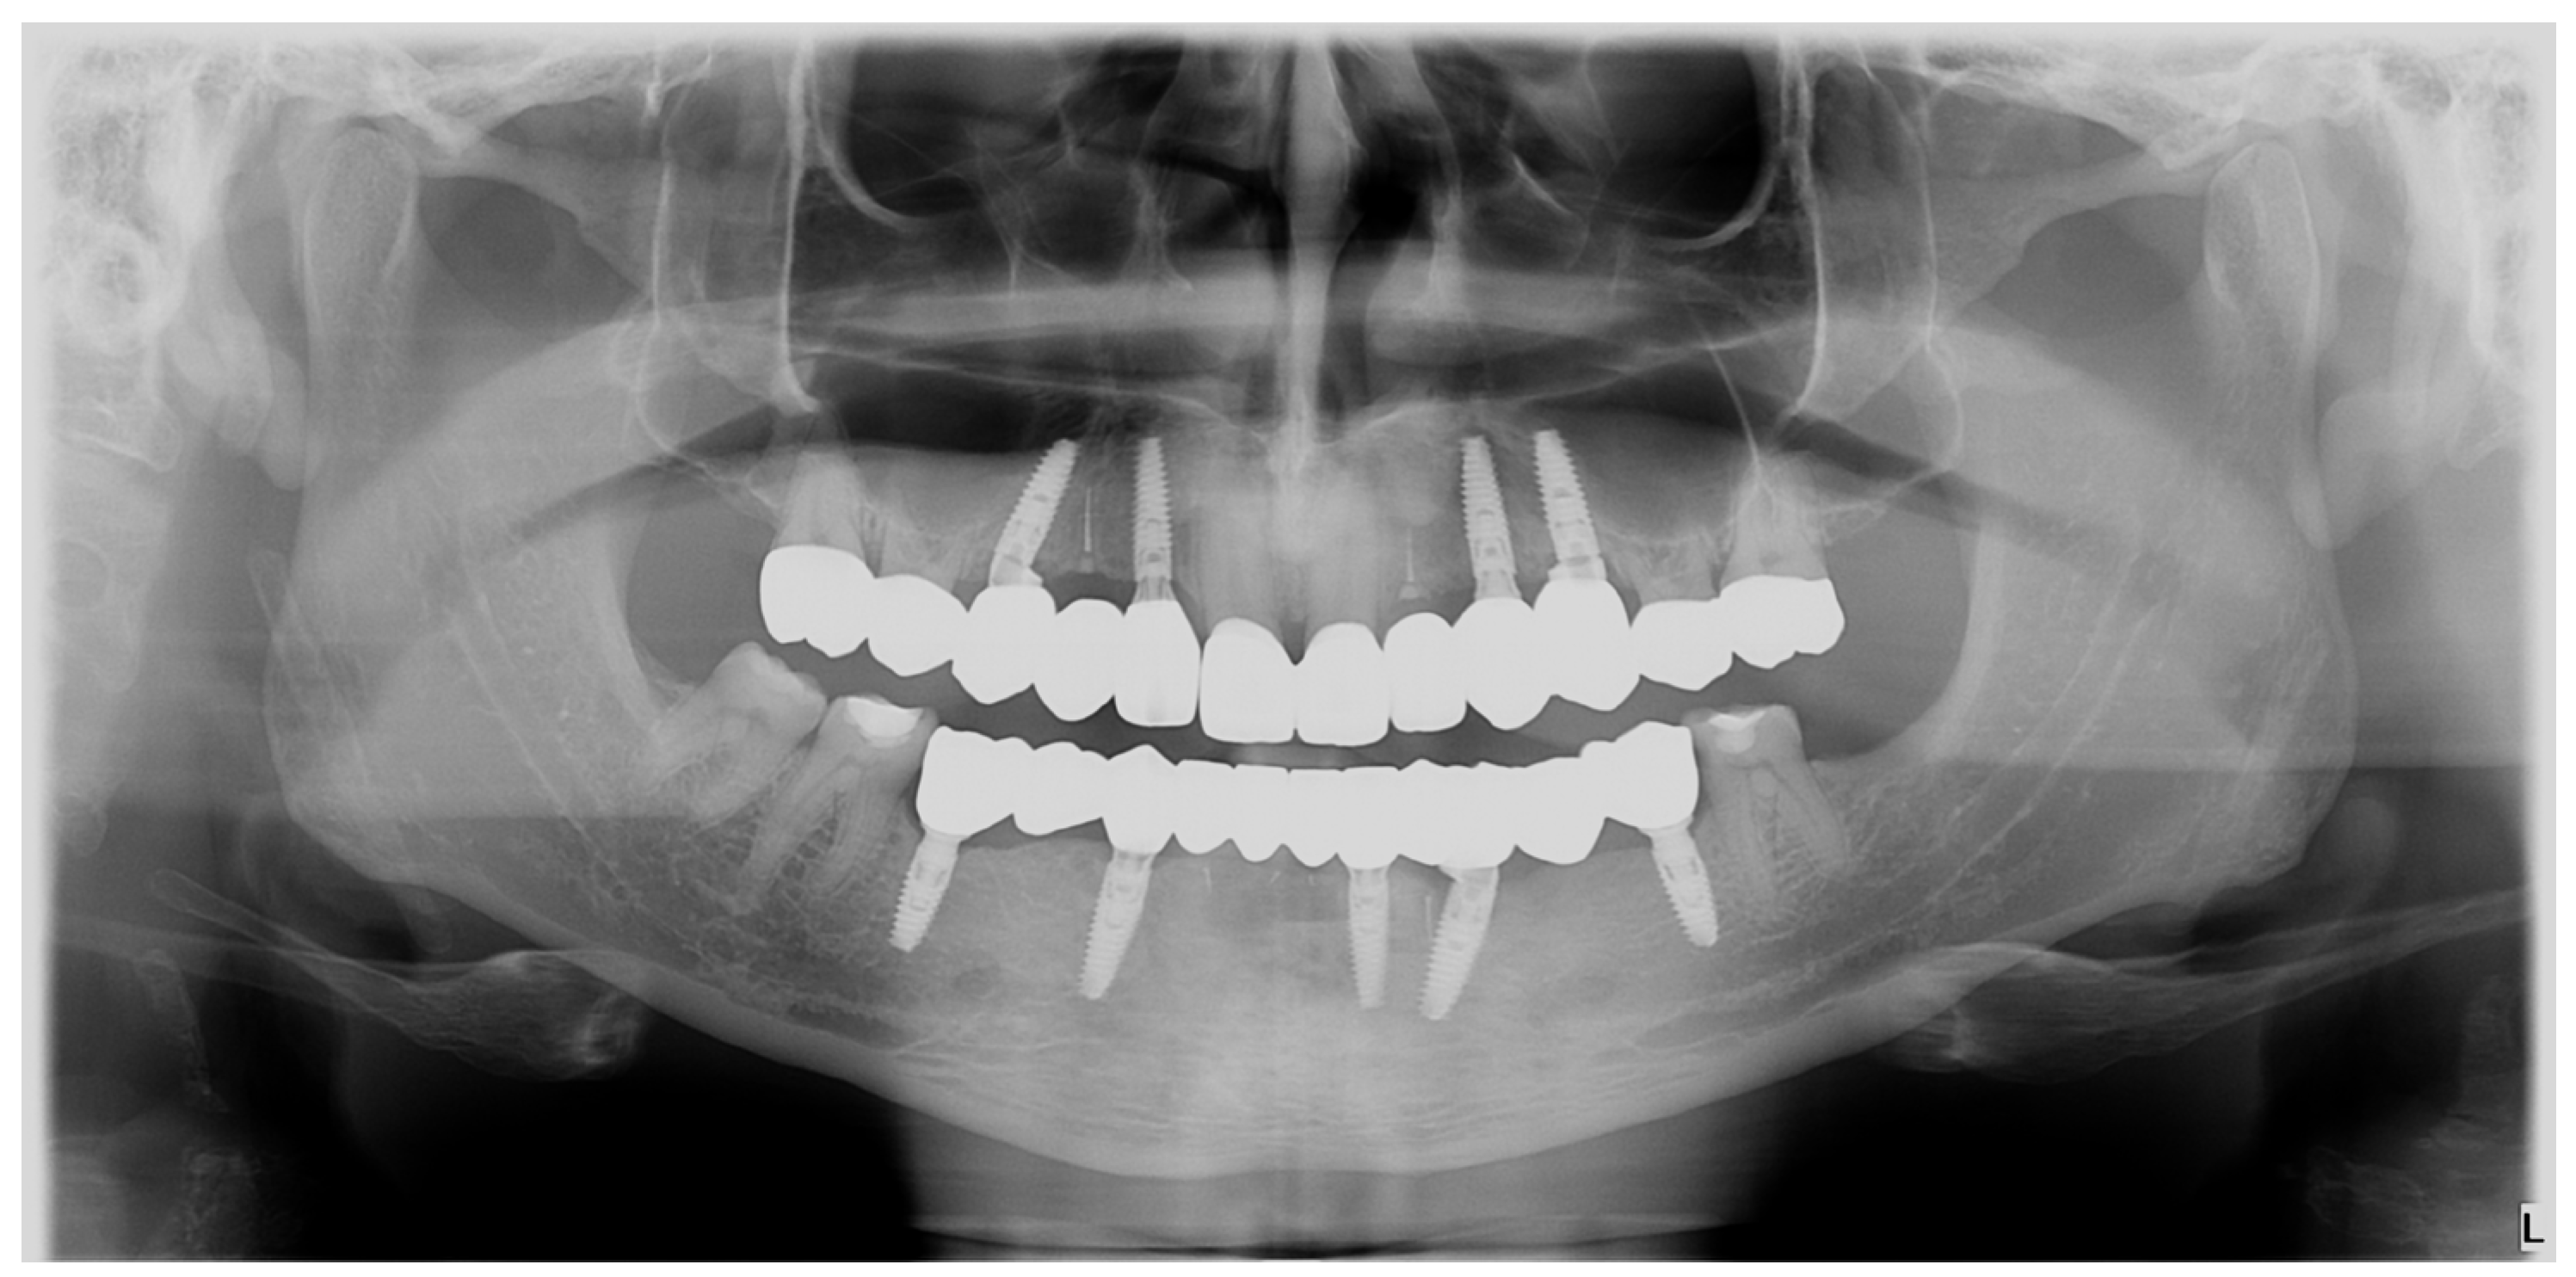

Also, at the three-year recall, the radiological (Figure 23) and clinical (Figure 24) result was well maintained.

Figure 23.

OPG: three-year radiological recall.